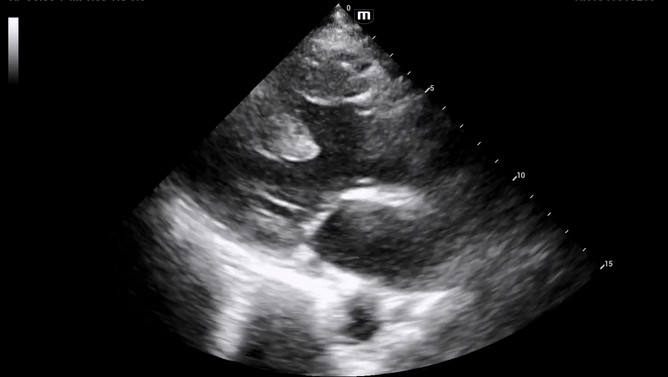

Decision was made to perform limited beside echocardiogram:

Initial POCUS shows abnormality in the ventricular septal wall (PSL 1 above), and upon putting color doppler, imaging was highly suspicious for a VSD.

The patient's aortic outflow tract also appeared to be enlarged and received flow from both the LV and RV, concerning for an “overriding aorta” (PSL 2 above).

Additional views were obtained showing RV strain (likely chronic) in the PSS (below) as well as significantly enlarged RA and RV chambers, as noted in the A4C view (below).